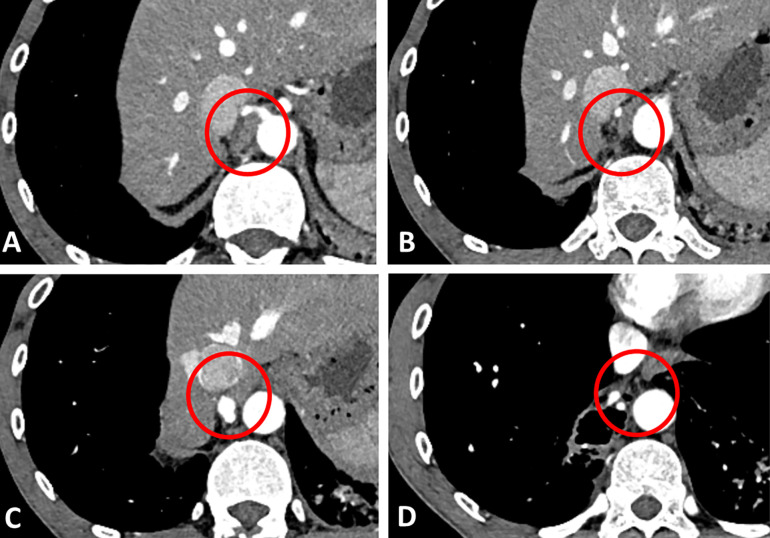

Background: Pulmonary sequestration is a congenital malformation in which nonfunctional lung tissue develops without connection to the bronchial system. The main complication is the occurrence of recurrent pneumonia.

Case presentation: We describe the case of a patient who was incidentally diagnosed with PS as part of the diagnostic algorithm for community-acquired pneumonia. Due to the relatively late diagnosis, the recurrent bronchopulmonary was conducive to the development of COPD and pulmonary emphysema. For prognostic reasons, surgical resection was performed by posterolateral thoracotomy.